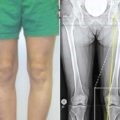

- искривление большого ручного пальца;

- видимые изменения по виду всех пальцев на руке (происходит искривление фаланг пальцев);

Ризартроз – деформация большого пальца на руке.